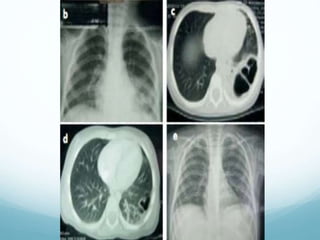

Teleradiografía de tórax

Imagen de

hiperclaridad

circunscrita, de

forma, contorno y

tamaños variables.

Abscesos

pulmonares

circunscrita,

delata un nivel

hidroaéreo

Quistes pulmonares

Teleradiografía de tórax Imagen de hiperclaridad circunscrita, de forma, contorno y tamaños variables.

Abscesos pulmonares Hiperclaridad circunscrita, delata un nivel hidroaéreo